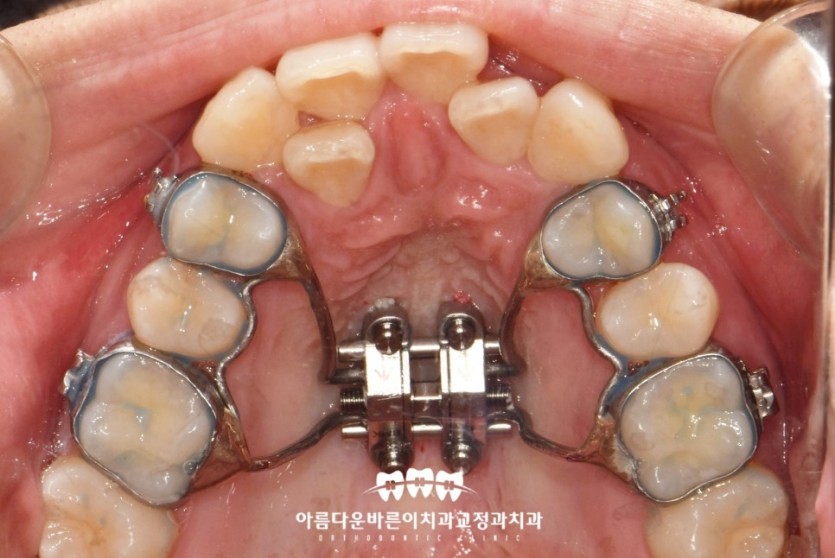

반면, 입천장의 가운데 부위 뼈가 완전히 굳은 성인의 경우에는

아래 사진처럼 미니스크류를 사용한 악궁 확장장치 (MARPE)를 사용해야 성공률이 높습니다.

3a9fb5be39523d14915d6c400783feb2_1663555569_5945.jpg